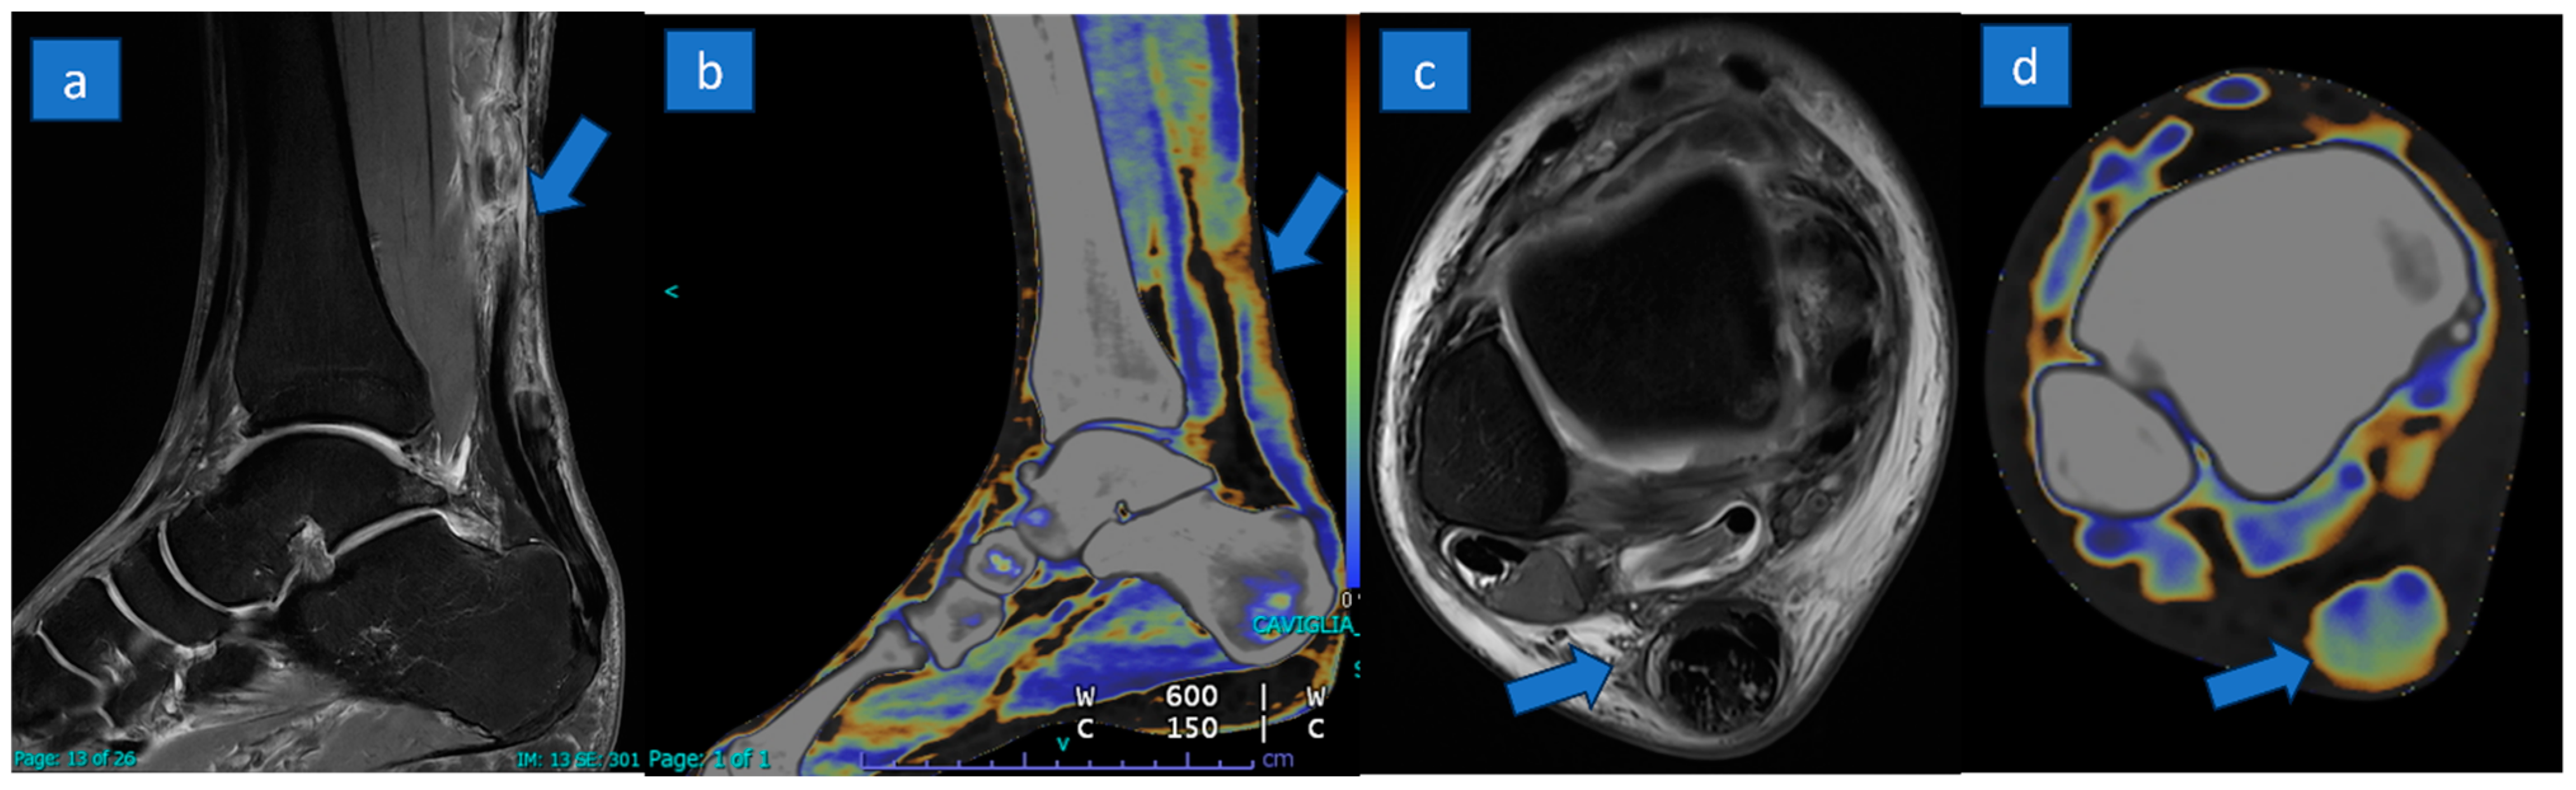

Figure 3.

A 27-year-old professional soccer player with a complete rupture of the proximal tendon. A complete tear with tendon retraction (arrow) is depicted on sagittal PD Fat-saturated MR image (a) and confirmed on the corresponding sagittal reconstructed DECT super-imposed color-coded image (b). Severe tendon thickening (arrow) with mild inflammatory changes is recognizable on the distal aspect with a good correlation between MRI (c) and DECT (d) axial images.